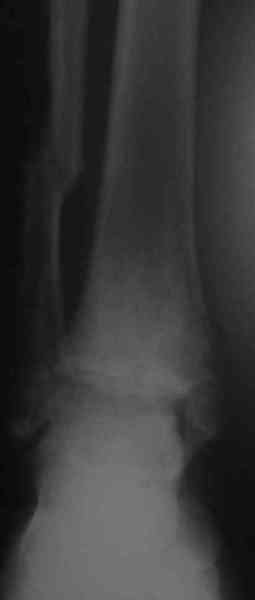

Уважаемые коллеги! Хотел-бы продолжить разговор об исходах переломо-вывихов в голеностопном суставе. При этом, в данном конкретном случае, хотелось узнать мнение опытных коллег об эндопротезировании. На консультацию обратилась пациентка, 26лет. В 2002 году открытый переломо-вывих. Лечение: вправление, трансфиксация спицами и гипсовая повязка. Около 4-х месяцев сохранялись явления нагноения вокруг спиц. На сегодня - движения в суставе отсутствуют, постоянные боли, функциональное укорочение конечности = 3 см. На недавней конференции по хирургии стопы и голеностопного сустава демонстрировался эндопротез НИИТО им. Вредена, внешне понравился. Юрий Алексеевич Булахтин